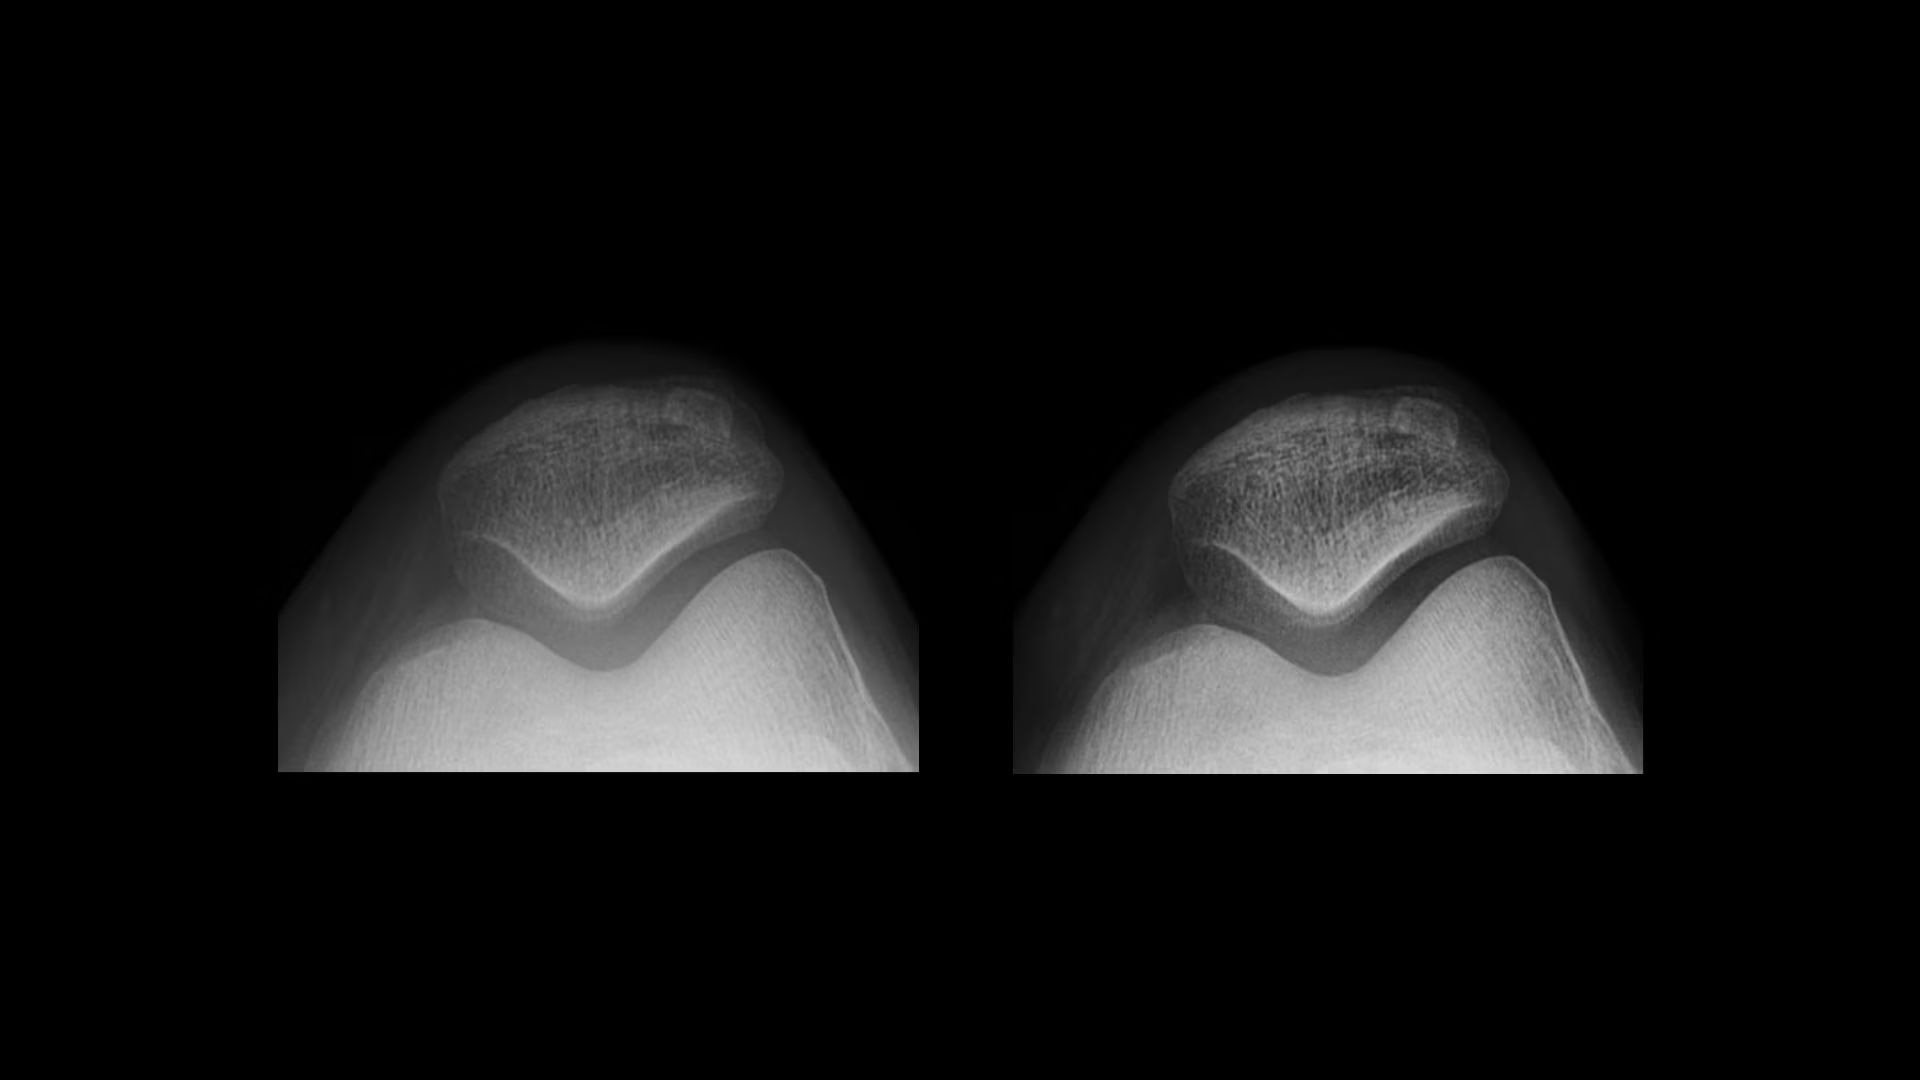

Clarity

Local Contrast Enhancement (LCE) increases local contrast in both pediatric and adult chest X-ray images for better visualization of the lungs, heart, and spine regions. It is also available for ankle joint (AP), foot (AP), and patella (tangential)*, and has three levels of enhancement (low, medium and high).